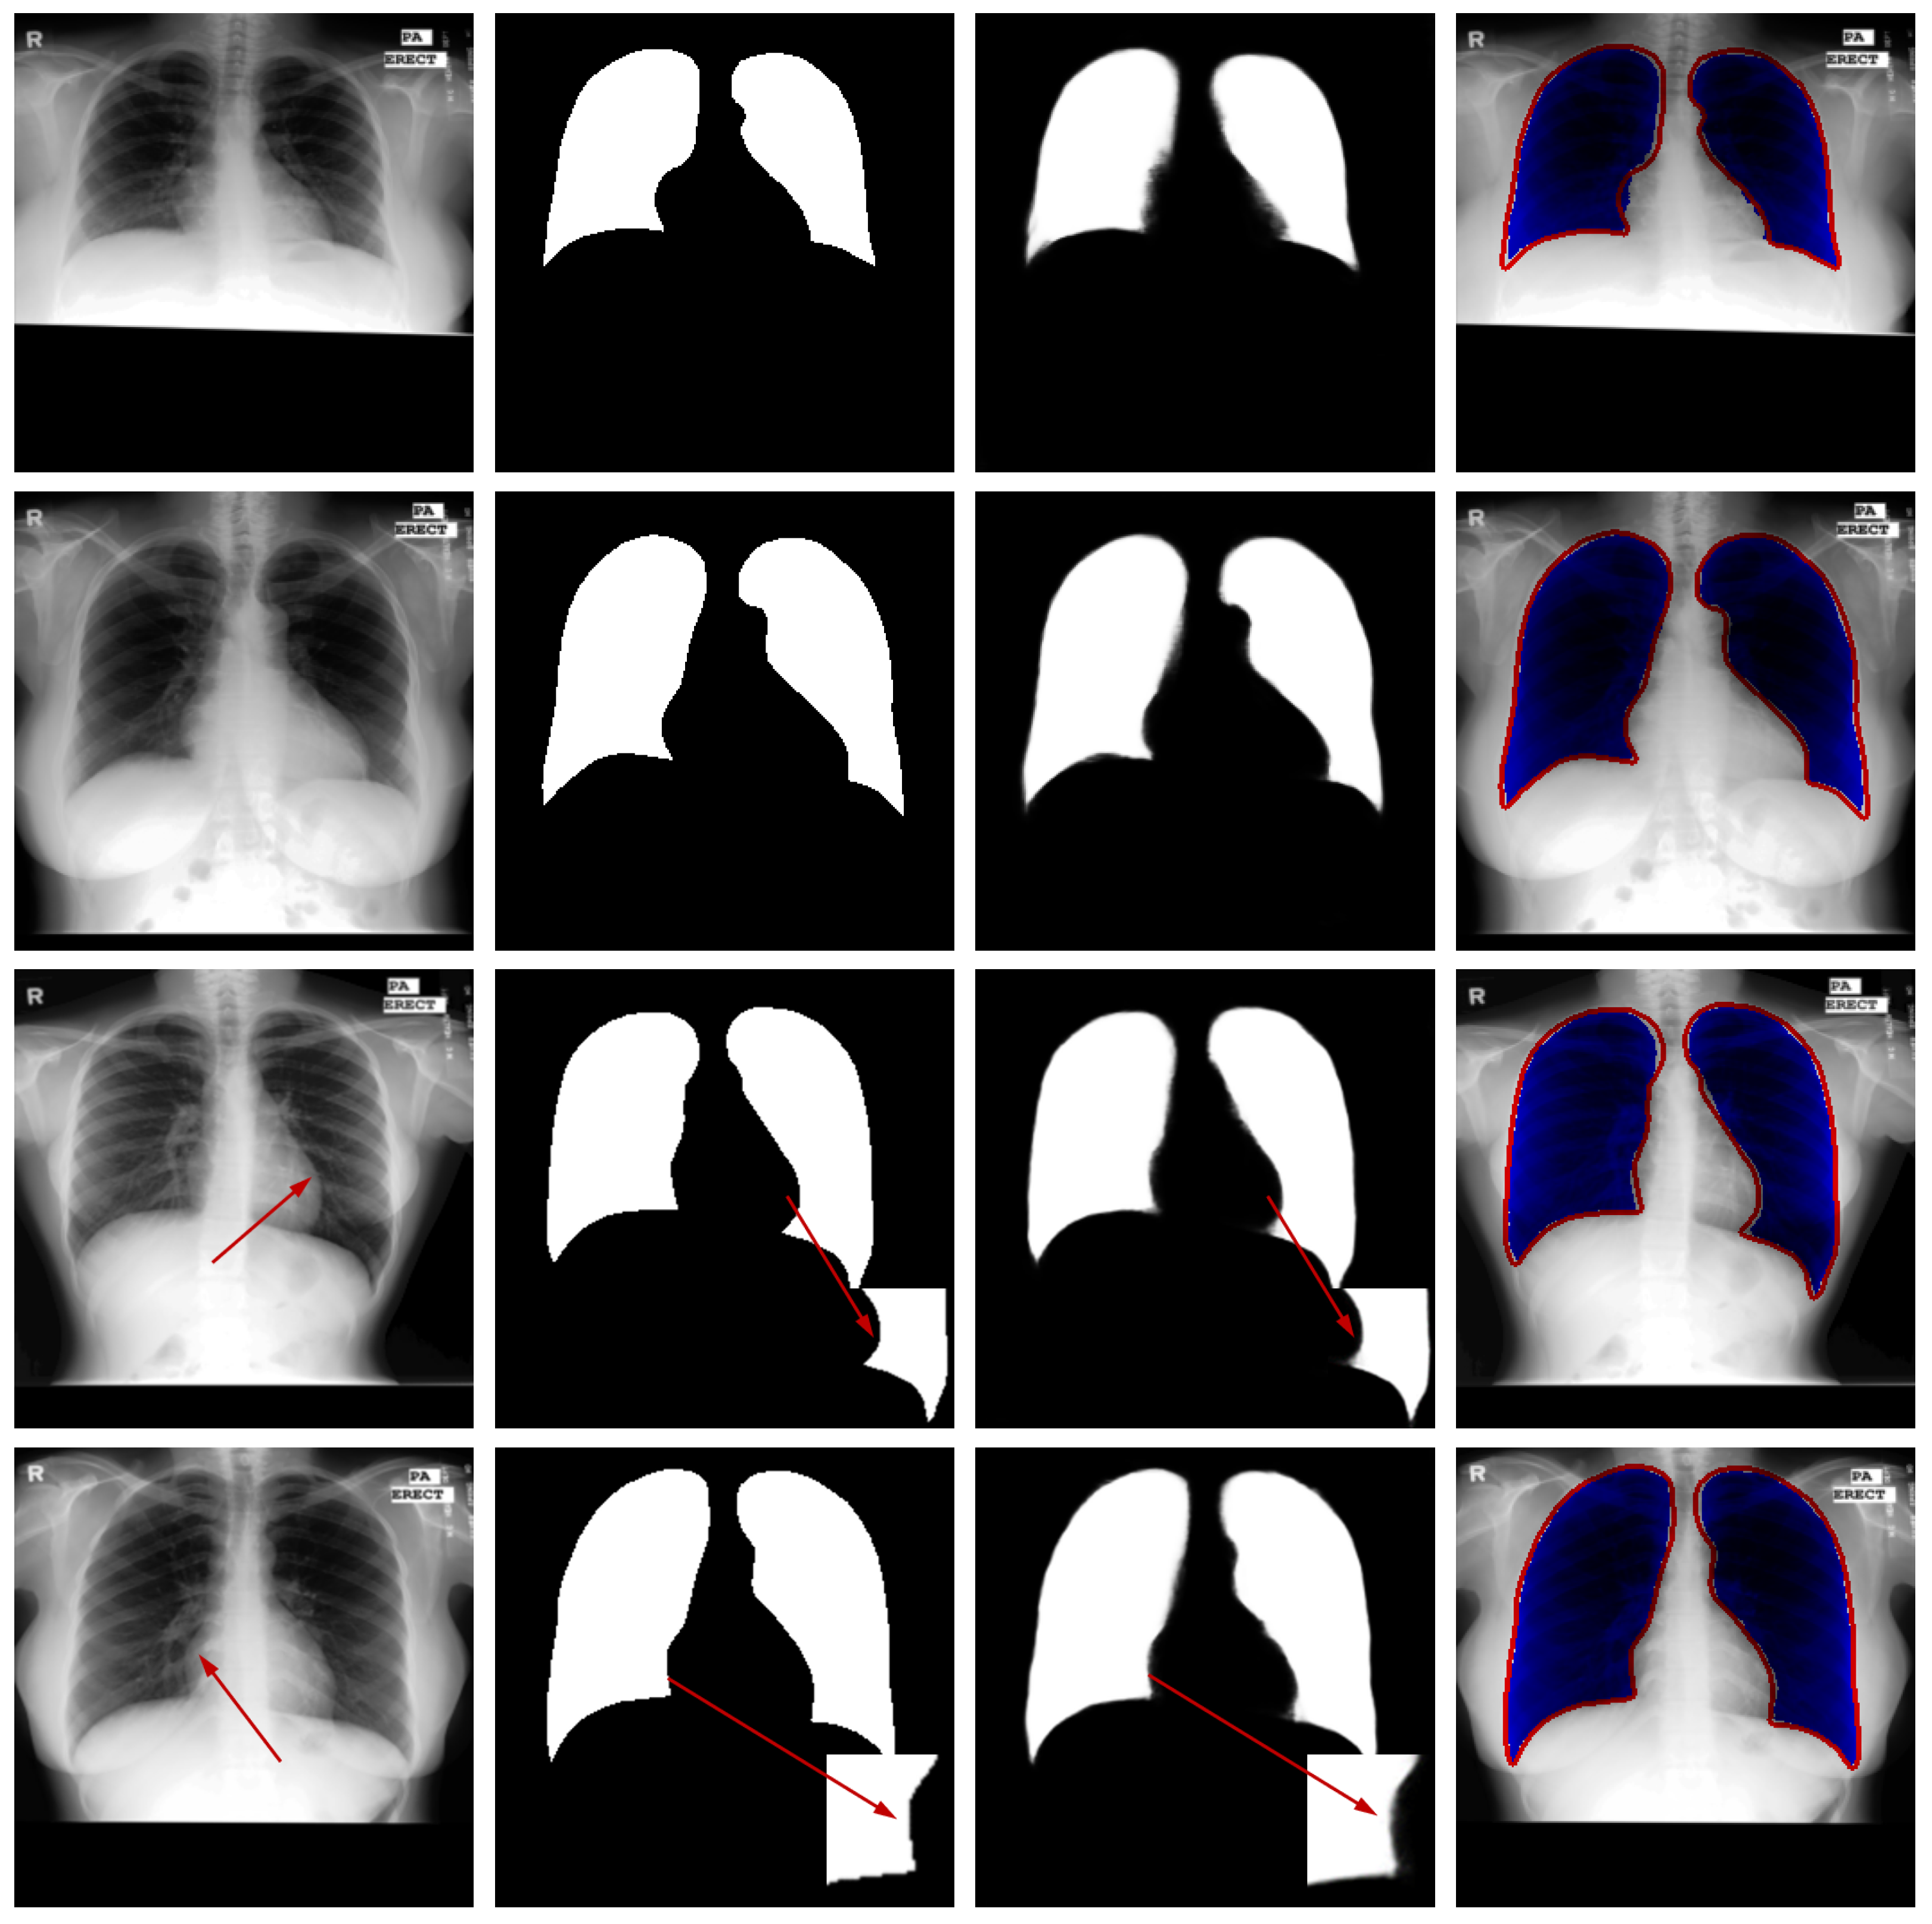

Qualitative Analysis: To visually evaluate the segmentation performance, Figure 4 presents a series of test cases from the Luna16 dataset, with a specific emphasis on challenging scenarios such as low-contrast boundaries, irregular lung shapes, and the presence of adjacent anatomical structures with similar intensities.

Figure 4.

Representative samples from the testing phase. From left to right: input image, ground truth mask, predicted segmentation, and the difference map between prediction and ground truth. The red arrows in the third and fourth rows of the first column in the figure represent difficult recognition areas, the red arrows in the second column represent corresponding ground truth image edge areas, and the red arrows in the third column represent difficult recognition edges in the predicted image. The blue area in the fourth column represents the predicted areas, and the red part represents the ground truth contour.

The results demonstrate that our model generates segmentation masks with crisp boundaries and accurate anatomical alignment. Crucially, as highlighted in the third and fourth rows of Figure 4, the network maintains high precision even in regions where the contrast between lung tissue and the surrounding pleura is very low—a common failure point for many segmentation methods. The difference maps (rightmost column) are included to provide a comprehensive view of the discrepancies, which are minimal and predominantly located at the most subtle boundaries, thus underscoring the overall high accuracy of our method.

These visual observations corroborate the quantitative findings and confirm the model’s robustness in handling the inherent complexities of lung CT segmentation.